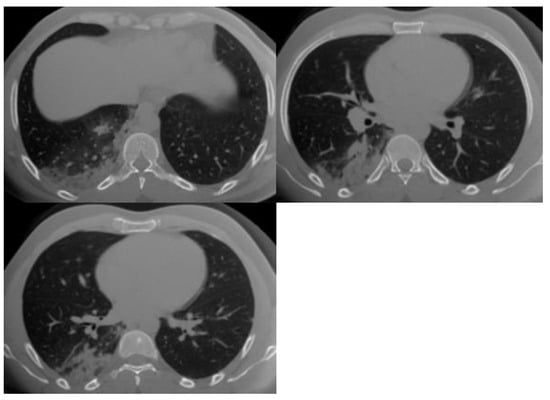

| 1 | Very low | Normal or non-infectious CT findings. |

| 2 | Low | CT findings incompatible with COVID-19: bronchitis, infectious bronchiolitis, and bronchopneumonia. |

| 3 | Equivocal/uncertain | CT findings of other viral pneumonia or non-infectious results: perihilar GGO, homogenous extensive GGO, and GGO with smooth interlobular septal thickening. |

| 4 | High | CT findings are similar to those for CO-RADS 5, but a lack of contact with the visceral pleura, located unilaterally, in a peri-broncho vascular distribution, or when the findings are superimposed on pre-existing lung abnormalities. |

| 5 | Very high | Typical CT findings: ground-glass opacities with or without consolidations in lung regions close to visceral pleural surfaces and multifocal bilateral distribution. |